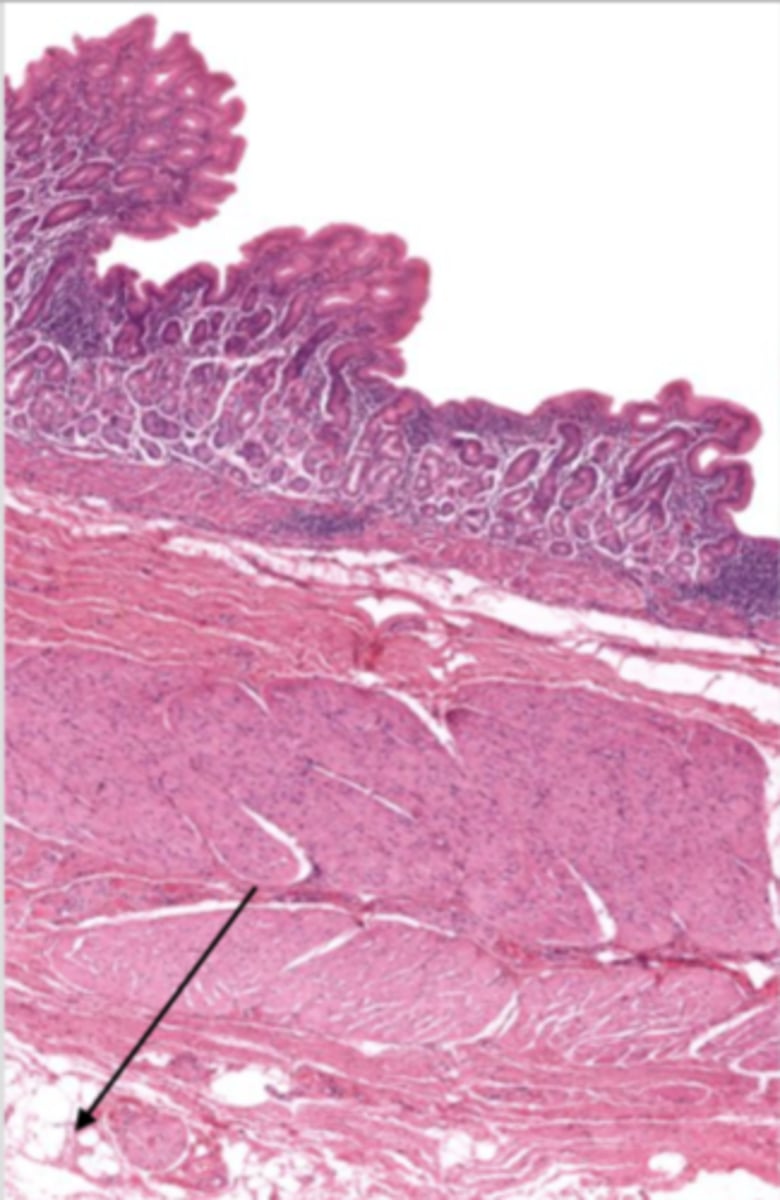

esophagus (histology)

lumen (esophagus)

mucosa (esophagus)

mucosal epithelium (esophagus)

stratified squamous epithelium

what kind of epithelium lines the mucosa of the esophagus?

lamina propria (esophagus)

muscularis mucosa (esophagus)

submucosa (esophagus)

contains glands and blood supply

muscularis externa (esophagus)

serosa/adventitia (esophagus)